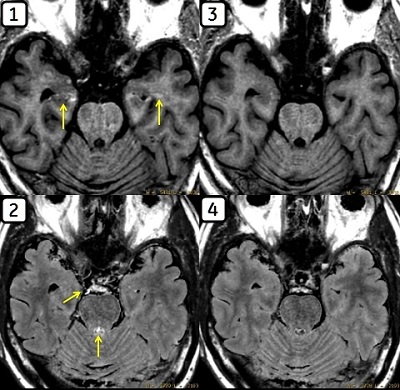

The figure below illustrates an example of differences between a MAGiC T2 FLAIR image compared with a conventional T2 FLAIR.

Figure 1. Conventional T2FLAIR image head versus a MAGiC T2W FLAIR image

Table 1. Image legend

NumberDescription

1Conventional T2 FLAIR

2MAGiC T2W FLAIR

A = Hyperintense Vessel Sign (HVS)

B = High signal intensity at the edge of Cerebral Spinal Fluid (CSF)

C = CSF

Flow artifact considerations

The MAGiC MDME sequence is susceptible to flow artifacts, as is any FSE technique. Due to the application of multiple inversion pulses, this is more apparent in certain situations on MAGiC-derived series

The figure below illustrates an artifact related to pulsatile flow phenomena. Image 1 shows a MAGiC T1 FLAIR image with artifact likely resulting from fast flowing blood. Image 2 shows a MAGiC T2 FLAIR displaying artifact related to CSF flow. Images 3 and 4 present with a notable reduction in artifact as a result of using the recommended parameter settings.

Figure 2. Pulsatile flow phenomena

Table 2. Image legend

1T1 FLAIR

2T2 FLAIR

3T1 FLAIR + I SAT

4T2 FLAIR + I SAT

Recommendation: Minimize this artifact by maintaining a slice gap of 10% or larger of the acquired slice thickness. The addition of an inferior saturation region within the imaging FOV can aid in suppressing this artifact. You may also acquire MAGiC in a different orientation for further artifact reduction.